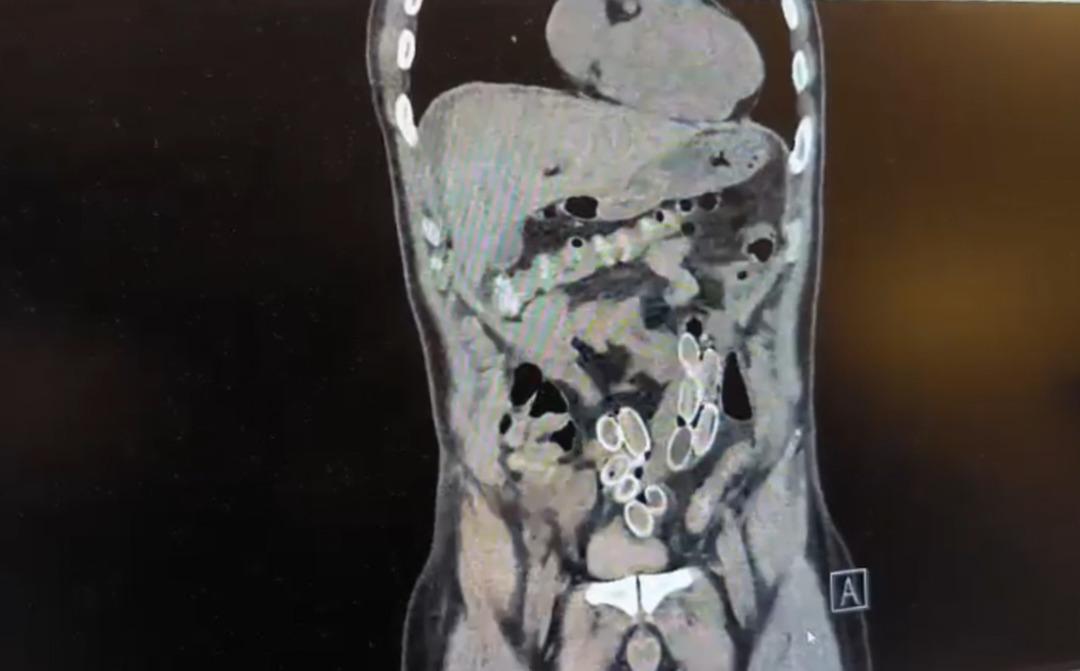

İhbar üzerine çalışma başlatan Beşiktaş Asayiş Büro Amirliği ekipleri, doktorlarla görüşme gerçekleştirdi. Doktorların değerlendirmesi sonrası ameliyata alınan Cüneyt Ç.’nin bağırsaklarından, toplam ağırlığı 259,7 gram olduğu öğrenilen 49 esrar macunu çıkarıldı. Şüpheliye ait 1 adet cep telefonu da hastane yetkilileri tarafından polis ekiplerine teslim edildi.